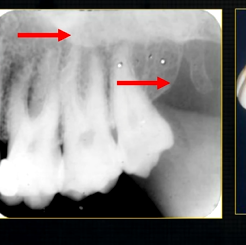

1st image taken using the bisected angle technique

2nd was taken using the geometrically accurate, paralleling technique

upper image is geometrically distorted

shadow caused by zygoma

this was taken using the bisected angle technique

x ray beam was directed below the zygoma

very lower of the zygoma is seen - projected above the apices

pterygoid hammulus - supports the muscles of the soft palate

coronoid process of the mandible